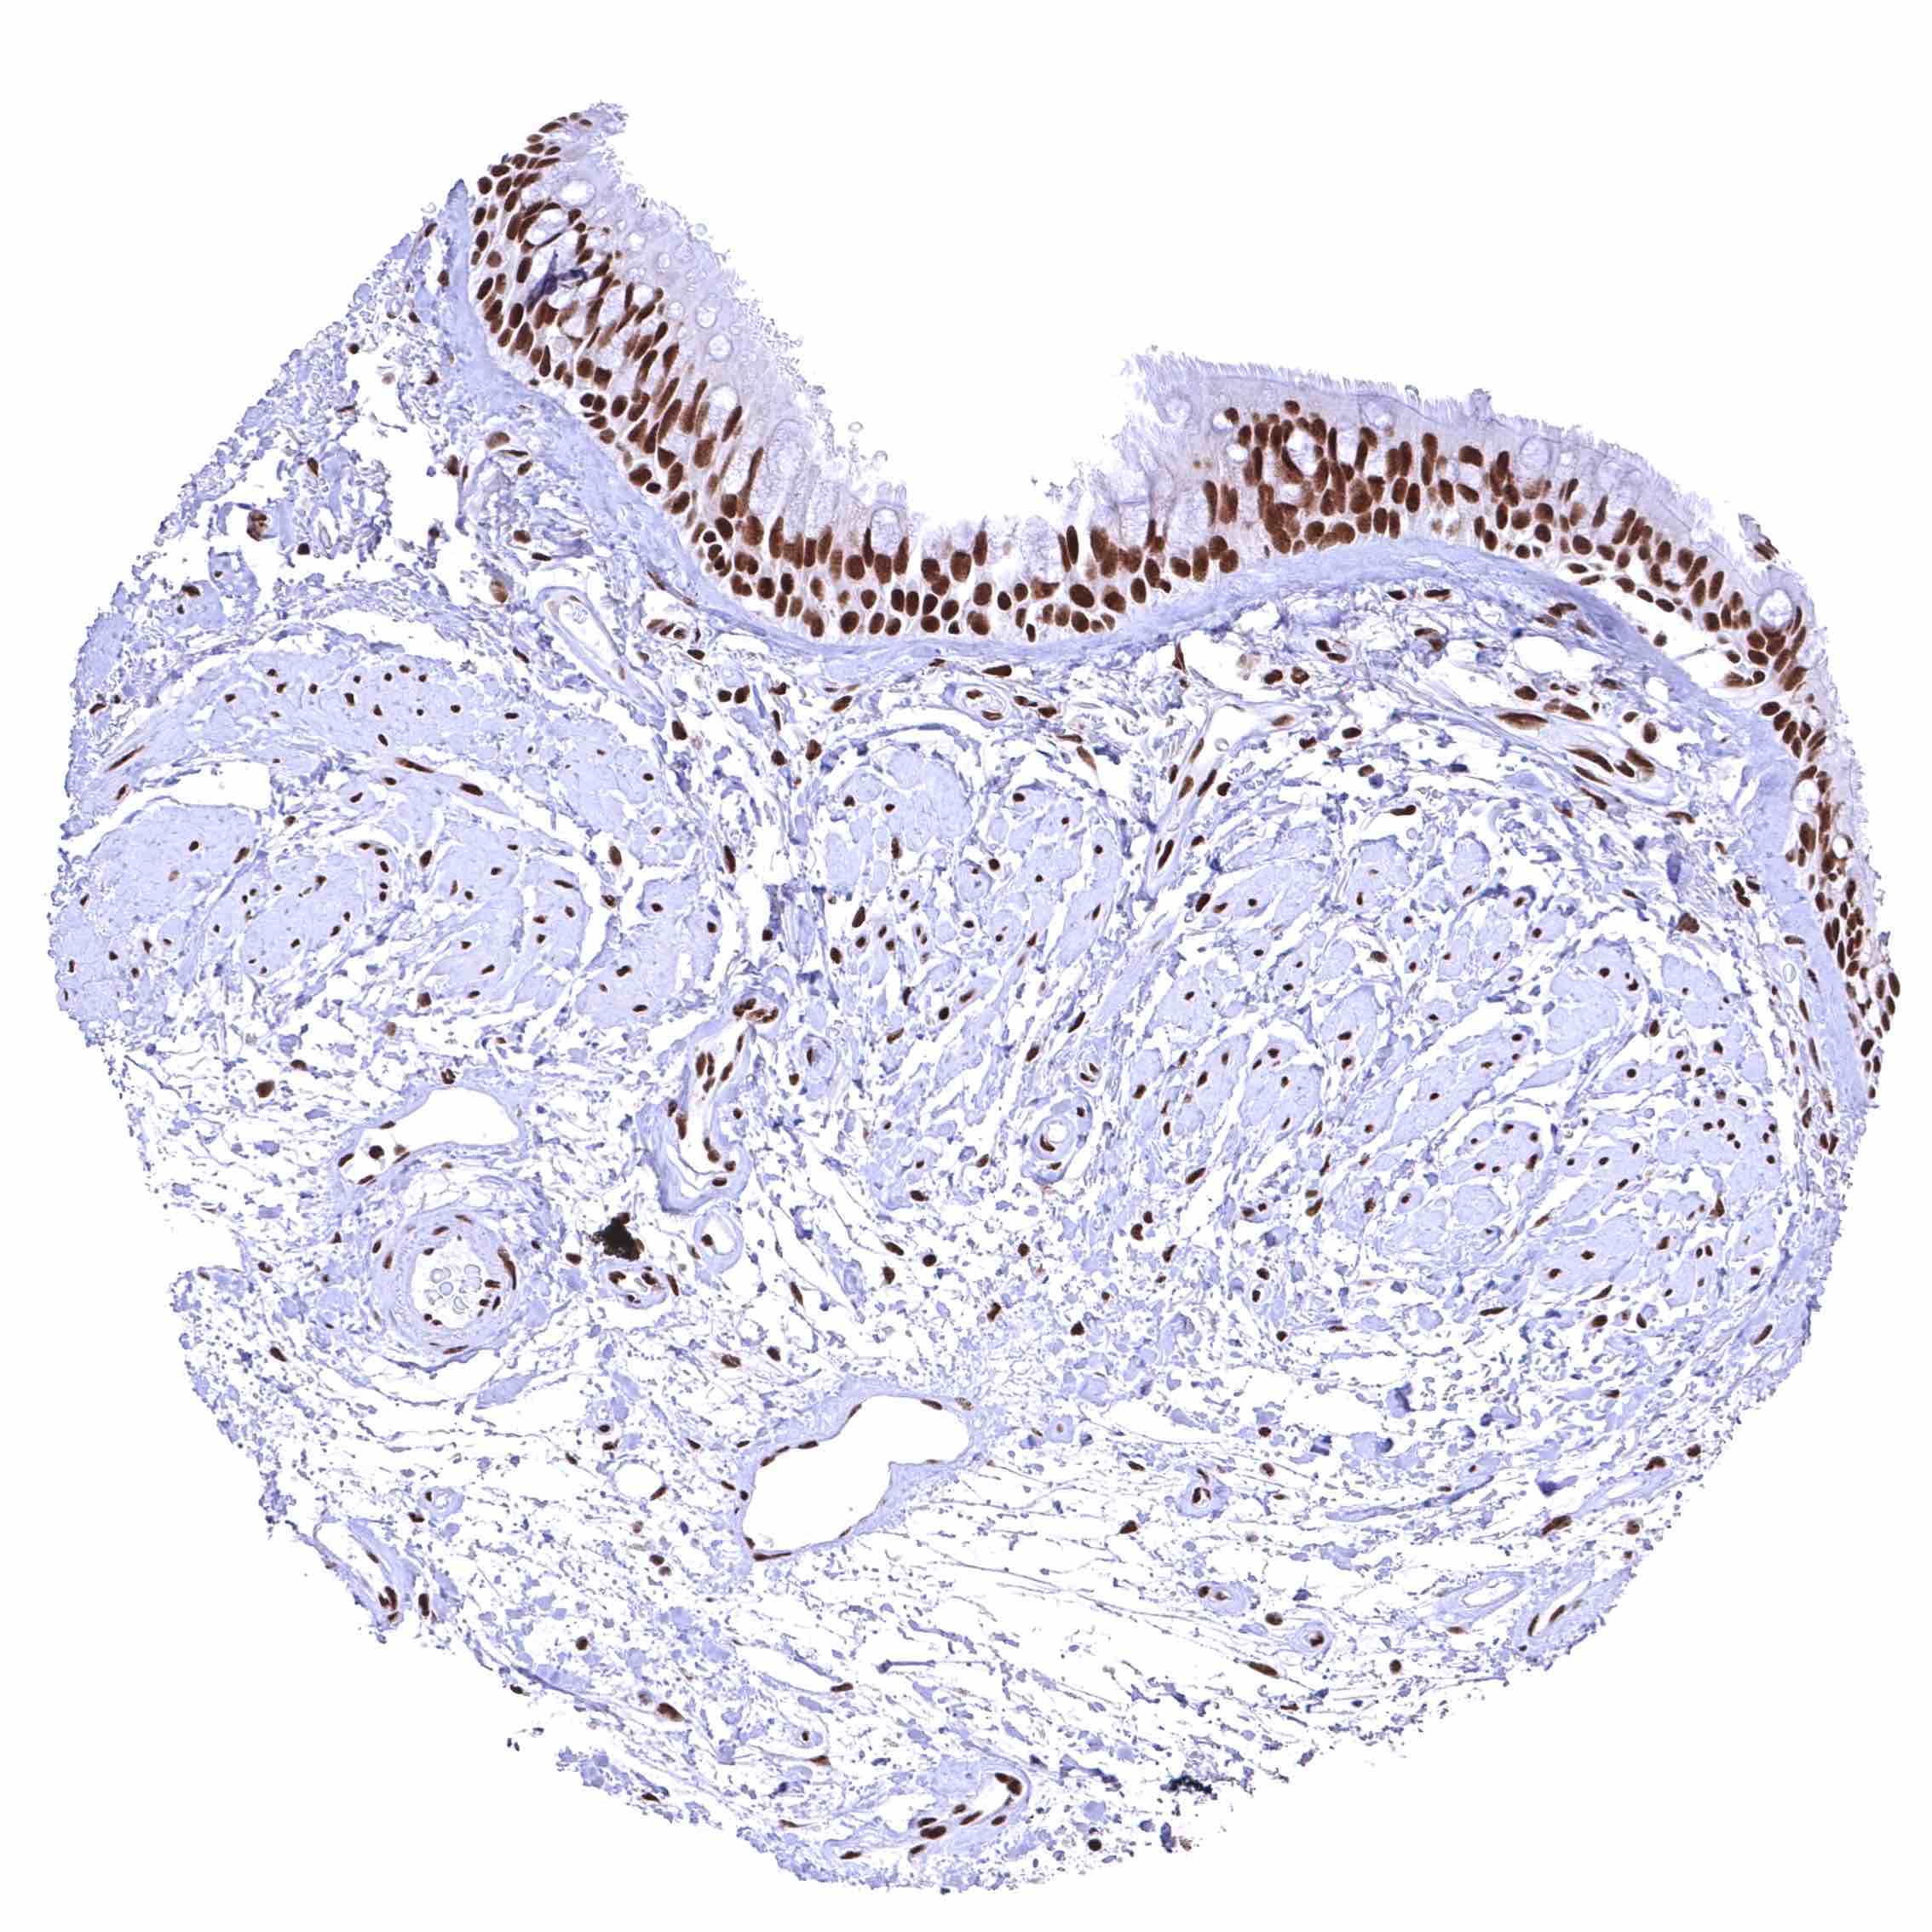

BRD4 antibody [HMV4275] HistoMAX™

Uterus, ectocervix – Distinct nuclear BRD4 staining of squamous epithelial cells with a slight decrease of the staining intensity towards the most superficial cell layers.